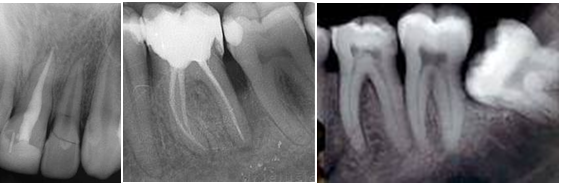

Endodontic therapy

This type of therapy has to be treated with maximum attention. During the roots treatment it is very important to obtain the maximum sterilizated area in order to have the necessary criteria for a successful treatment.

We use manual or mecchanic treatment for root canals. The quality of the instruments that we use is very high.

RTG